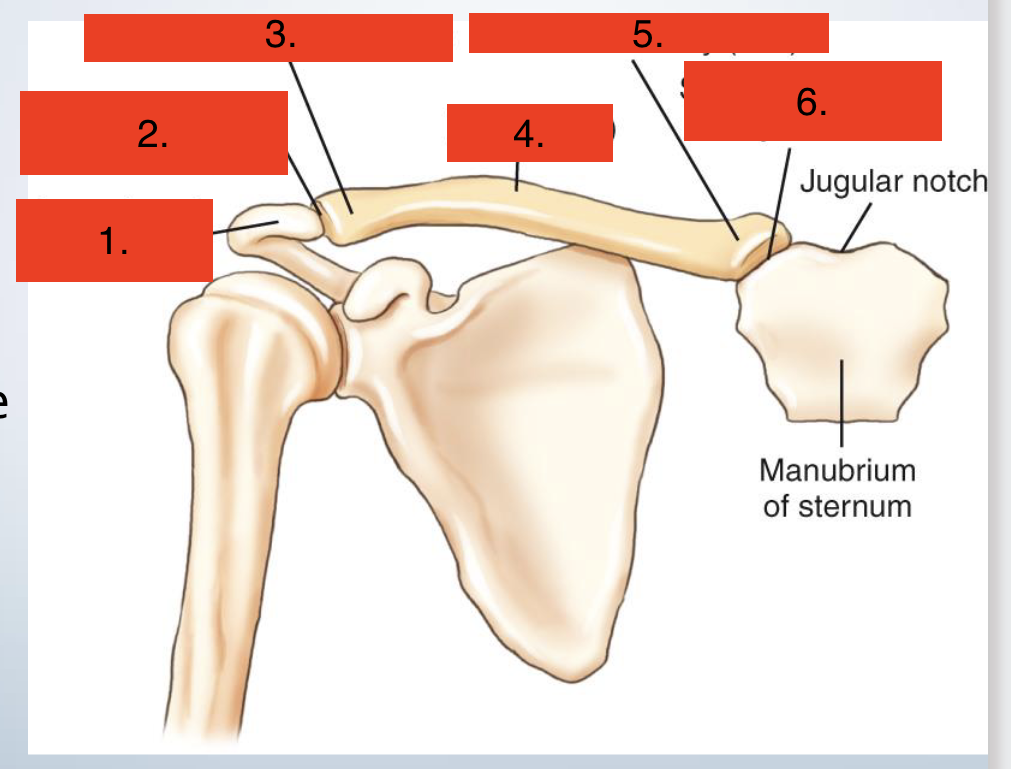

Shoulder Girdle

Scapula and clavicle

Articulates with - Head of humerus (shoulder joint), Manubrium of sternum (sternoclavicular joint), Clavicle to scapula (acromioclavicular joint)

Clavice

Acromion of scapula

Acromioclavicular joint

Acroomial extremity (end)

Body

Sternal extermity (end)

Sternoclavicular joint